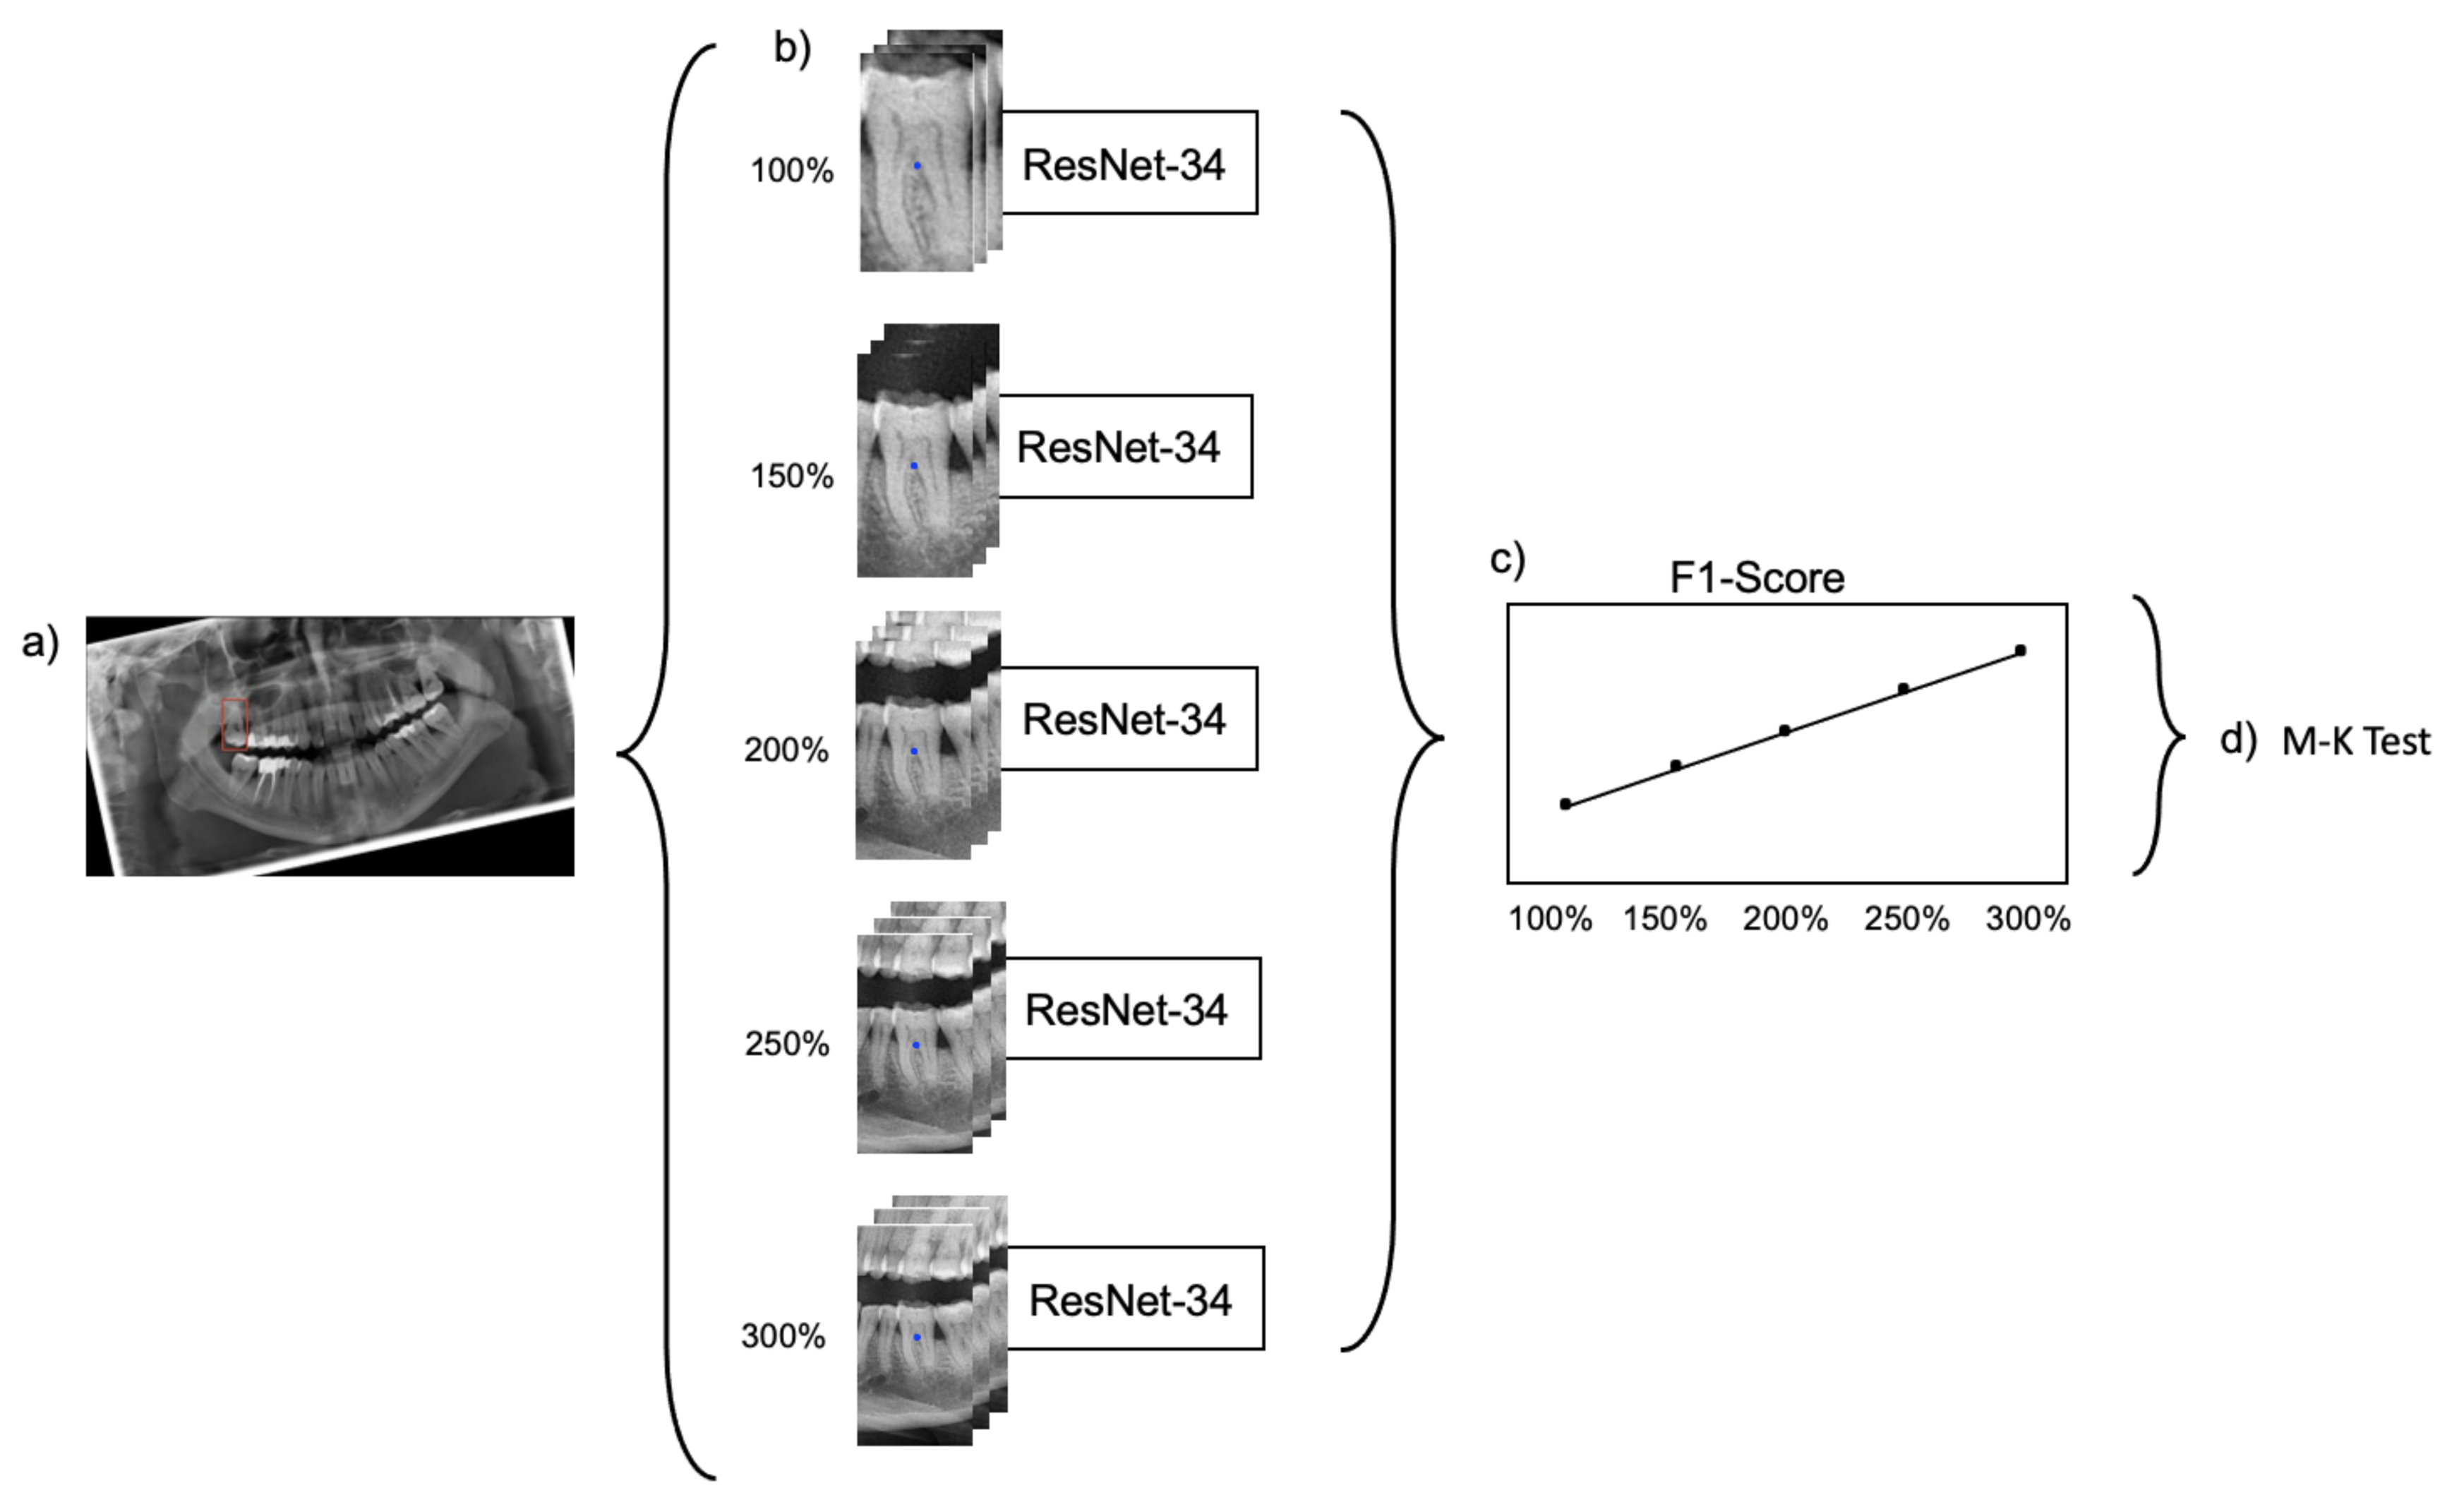

Cropping was repeated five times, each time with varying regional context information: The baseline bounding box size (100%) was scaled up to capture 150%, 200%, 250% and 300% of the baseline bounding box. The original aspect ratio was kept constant (see

Figure 1). Note that the tooth considered for the classification task was consistently located within the center of each image segment.

The generated datasets were used to train five ResNet-34 classification models with the same set of hyperparameters. ResNet-34 has 34 layers and consists of a stack of residual blocks of CNNs that function as a feature extractor and a fully connected classification head (

Supplementary Figure S1). The model outputs a score for each possible label for the tooth located in the center of each input image. The label with the highest score was considered as the model’s prediction. Training, validation and testing of each model was exclusively performed on the dataset with the dedicated image segment size.

Figure 2 provides a summarizing overview of the workflow.

For hypothesis testing, the Mann–Kendall (M-K) test [

8], a nonparametric test for monotonic trends was applied on the series of F1-scores resulting from the trained models. In this study, a monotonic upward trend was characterized by a consistent increase of the F1-score through the extending context of the image segments. A significance level of <0.05 was considered statistically significant.

When testing the base-case model, classification accuracy was 0.77, as was the F1-score, with a sensitivity of 0.74 and specificity of 0.99. Increasing the context, i.e., upscaling the image segment, increased the accuracy, with the maximum segment size of 300% yielding an accuracy, a F1 score and a sensitivity of 0.93, at a continuously high specificity of 0.99 (

p = 0.0083; M-K test).